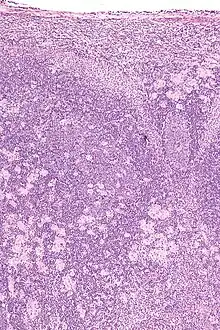

Real-time PCR is useful in pathogen detection, gene expression and regulation, and allelic discrimination. This PCR technique utilizes the 5' nuclease activity of Taq DNA polymerase to cleave a nonextendible, fluorescence-labeled hybridization probe during the extension phase of PCR.[63] A second fluorescent dye, e.g., 6-carboxy-tetramethyl-rhodamine, quenches the fluorescence of the intact probe.[63] The nuclease cleavage of the hybridization probe during the PCR releases the effect of quenching resulting in an increase of fluorescence proportional to the amount of PCR product, which can be monitored by a sequence detector.[63] Lymph nodes affected by Toxoplasma have characteristic changes, including poorly demarcated reactive germinal centers, and scattered epithelioid histiocytes.[64]